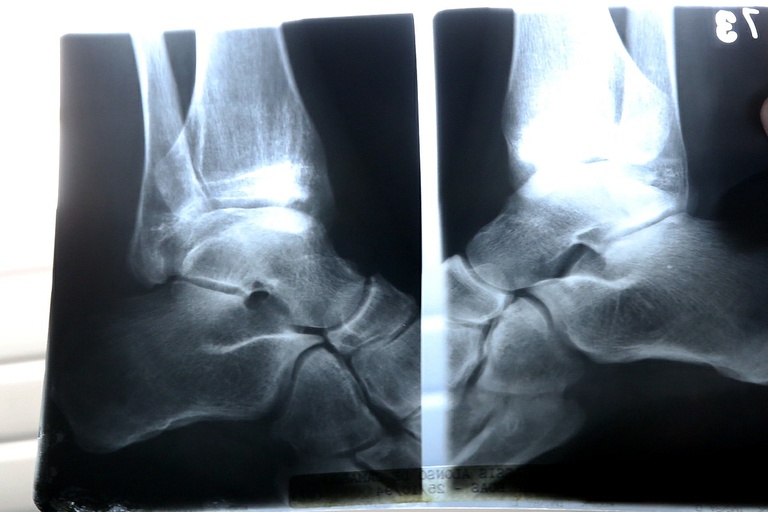

A escolha de 20 de outubro é uma iniciativa da Fundação Internacional de Osteoporose (International Osteoporosis Foundation – IOF), que tem o objetivo de “conscientizar as pessoas sobre os cuidados que se deve ter para prevenir a doença, que já é considerada o segundo maior mal ao nível mundial, ficando atrás apenas das doenças  cardiovasculares. A osteoporose, a partir dos 50 anos, atinge 1 em cada 3 mulheres e 1 em cada 5 homens”, diz a justificativa do projeto (005.00278.2017).

A população com mais de 60 anos vai aumentar de 14 para 58 milhões nos próximos 45 anos, de acordo com pesquisas do IBGE (Instituto Brasileiro de Geografia e Estatística). Deste total, 10 milhões serão acometidos pela osteoporose. “Considerando que a Lei Municipal foi aprovada antes da lei Estadual e que no mundo inteiro e no Estado do Paraná, a data da Conscientização da Osteoporose é dia 20 de outubro, não há porque em Curitiba ser instituída no dia 03 de maio”, argumenta Maria Leticia.